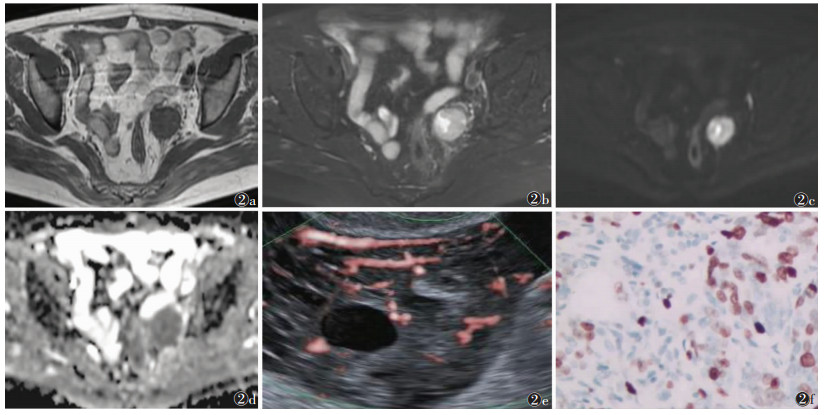

| 注:患者,女,56岁。图 2a为T1WI,示左侧附件区肿瘤呈低信号;图 2b为T2WI,病灶呈稍高信号;图 2c为DWI,病灶呈高信号;图 2d为ADC图,病灶呈低信号,ADC值0.956×10-3 mm2/s;图 2e为SMI,示右侧附件区肿瘤见2条较长血管;图 2f为病理图(HE染色,高倍放大),光镜下见肿瘤细胞内棕褐色深染颗粒,Ki-67低表达(30%) 图 2 卵巢癌患者MRI、超微血管成像(SWI)及病理图像 |

2 结果74例中,高表达组46例,低表达组28例。2组临床特征差异无统计学意义(P > 0.05)(表 1)。高表达组的血管数量多于低表达组,ADC值低于低表达组,差异均有统计学意义(均P<0.05)(表 2,图 1、2)。2位医师测量的ADC值一致性良好(ICC > 0.80)。